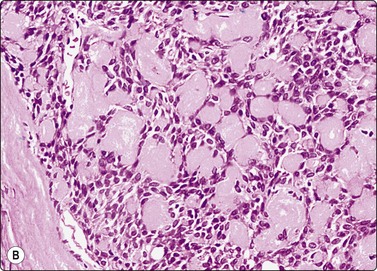

Paraganglioma (carotid body and glomus jugulare tumors) (Figs 4.11-4.13)5,50-52

image

Fig. 4.11 Paraganglioma

CT scan showing large solid mass in left oropharynx; paraganglioma diagnosed by FNB.

image image

Fig. 4.12 Paraganglioma

Loosely clustered cells; suggestion of follicular arrangement resembling thyroid epithelium; anisokaryosis and ‘speckled’ chromatin (Pap) typical of neuroendocrine tumors. Very fine eosinophilic cytoplasmic granules visible under the microscope but not in photograph; (A, MGG, HP; B, Pap, HP).

Fig. 4.13 Paraganglioma (atypical)

(A) Smear showing prominent anisokaryosis but a uniformly bland chromatin pattern (MGG, HP); (B) Tissue section of the same case (H&E, IP).

Criteria for diagnosis

Neoplastic cells single and loosely clustered, often forming curved rows or a vaguely follicular pattern; bloody background,

Abundant pale cytoplasm with indistinct cell borders,

A fine red cytoplasmic granulation (MGG) may be seen in some cells,

Nuclei rounded to spindle with granular or speckled, evenly distributed chromatin,

Variable anisokaryosis; scattered single cells with considerably enlarged nuclei, some bi-nucleate, in a background of generally uniform nuclei is characteristic,

Positive staining with neuroendocrine markers.

Problems and differential diagnosis

The cytological pattern is suggestive of an endocrine neoplasm and, given the anatomical site, the main differential diagnosis is a thyroid tumor. A follicular arrangement of the tumor cells may suggest a follicular carcinoma, but the fine red cytoplasmic granulation, the characteristic anisokaryosis and the presence of spindle cells closely resemble medullary carcinoma, and this is the main differential diagnosis (Fig. 4.12). Immune markers are helpful. Cells of paraganglioma stain positively for neuroendocrine markers. Staining for calcitonin is negative in most cases, but can occasionally be positive. Cytokeratin, thyroglobulin and TTF1 are negative. Intranuclear cytoplasmic inclusions as in papillary and some other carcinomas of the thyroid can be found in some paragangliomas.50 Knowledge of the exact anatomical site is obviously important. However, paraganglioma can occur in atypical locations including, although rarely, the thyroid. For example, one of our cases diagnosed by FNB had a tumor in the tonsillar region, clinically thought to be a deep parotid tumor (Fig. 4.11); another had a supraclavicular mass diagnosed clinically as lymphadenopathy. Both were histologically confirmed as paragangliomas.

Paraganglioma with a spindle cell pattern can mimic other spindle cell tumors in the neck such as spindle cell medullary carcinoma of thyroid and soft tissue tumors. Nuclear pleomorphism can sometimes be prominent enough to suggest malignancy (Fig. 4.13).5 As in other endocrine tumors, pleomorphism is not a reliable indicator of malignancy, mitotic rate and evidence of necrosis are better related to clinical behavior, and metastasis is the only definitive proof.

Paragangliomas are extremely vascular lesions and the aspirate often appears to be pure blood. If this is the case, smears may be non-diagnostic but diagnostic tissue fragments can sometimes be found in a cell block.